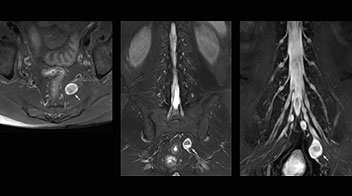

According to Tanji, methods such as ProSet FFE, STIR or 3D VISTA are anatomically nonselective because background signals, for instance from blood vessels, often interfere with nerves, which hampers evaluation of details, especially at the peripheral side of the nerves.

“The intra-luminal signal of veins, especially around the intervertebral space, can be suppressed well with NerveVIEW. As a result, we can easily observe the detailed nerve structure around the posterior ganglion,” he says. “This is why we use 3D NerveVIEW for intraforaminal stenosis and extraforaminal stenosis/herniation (lateral disc herniation). On the other hand, if herniation is suspected to exist inside the dorsal root ganglion (DRG), balanced TFE or ProSet-FFE is applied. NerveVIEW is not suitable for evaluating the median type of herniation.”

The SE-EPI DWI-based method for MR neurography works well for large FOV exams like whole-body MRI, but focal examination of nerves is often limited by the attainable spatial resolution (both inplane and slice direction) and geometric distortion. “3D NerveVIEW achieves higher in-plane resolution – close to our other routine spine sequences – and the source images can be used instead of adding a fat-suppressed T2-weighted sequence,” Tanji says.

Good spatial resolution is required

“For both brachial and lumbar plexus, we are currently using a 230 mm FOV and voxels of about 1 x 1 x 2 mm acquired (1 x 1 x 1 mm reconstructed). This provides us a good representation of the nerves, even though this FOV is relatively small. Regarding the inplane resolution, we hope to be able to bring that down to 0.7 mm, similar to our typical 2D multislice T2W images,” says Tanji.

“Recently, the two surgical methods extreme and oblique lateral interbody fusion (XLIF and OLIF) have become mainstream for minimally invasive treatment of lumbar spinal canal stenosis and intervertebral foramen stenosis. With these surgical techniques, the spine is approached from the flank, and prior knowledge of the exact anatomy of the lumbosacral plexus would be extremely helpful. To that end, high slice resolution (less than 1 mm acquisition) that enables sharper sagittal MPR images will be needed.”